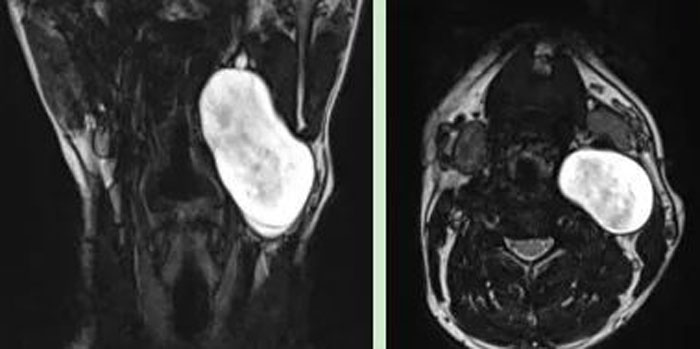

患者,男,26歲,2年前發現頸部左側腫物,逐漸增大,來我院就診。彩超示:左側頸部探及約5.0×4.3cm低回聲團塊;頸部MRI示:左側頸部囊性占位,考慮良性病灶,大小約3.5×5.1×7.2cm。

患者年紀輕,病情復雜,經充分準備后,在牛善利主任指導下,牛傳貴副主任醫師、步明強副主任在全麻下實施頸部腫物切除術。術中見腫物位于頸動脈鞘內,將頸內靜脈及迷走神經擠向外側,將頸內、外動脈擠向內側,腫物下緣至環狀軟骨水平,上緣至二腹肌后腹深面向上近顱底處。此次手術難度大,手術操作復雜,手術風險大,技術要求高,在手術室李蘊護士長、張建永護士長、楊凌主管護師及麻醉科鄧燕副主任醫師密切合作下,手術順利完成。病理參考免疫組化報告神經纖維瘤。術后患者恢復良好,已出院。(耳鼻咽喉科)